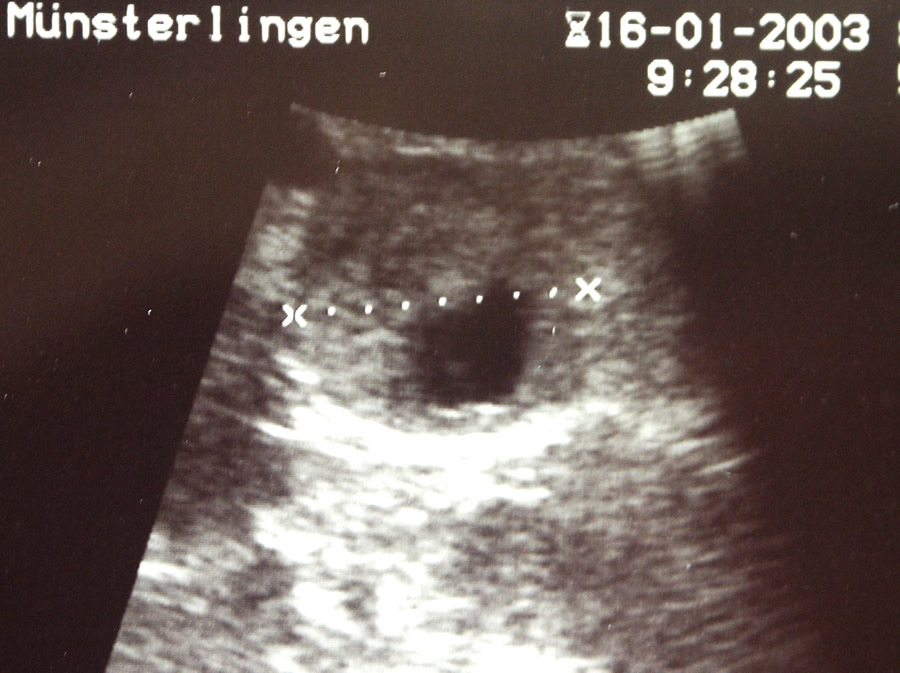

Das selbe gilt für die Behandlung der hormonproduzierenden Tumoren. Diese kleinen, häufig unter einem Zentimeter messenden Knoten produzieren z.B. Insulin im Überfluss und führen damit zur Unterzuckerung. Wegen ihrer geringen Grösse sind sie schwierig zu finden auch während der Operation. Während der Laparoskopie wird diese Lokalisation mittels einer Ultraschallsonde durchgeführt, welche direkt auf das Organ gelegt werden kann. (Ultraschallbild) Laparoskopisch oder offen chirurgisch werden die Tumoren ausgeschält oder mit etwas umliegendem Drüsengewebe entfernt.